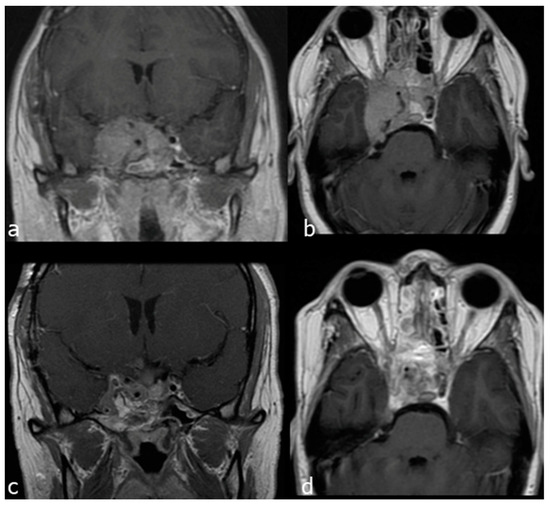

- Case 2